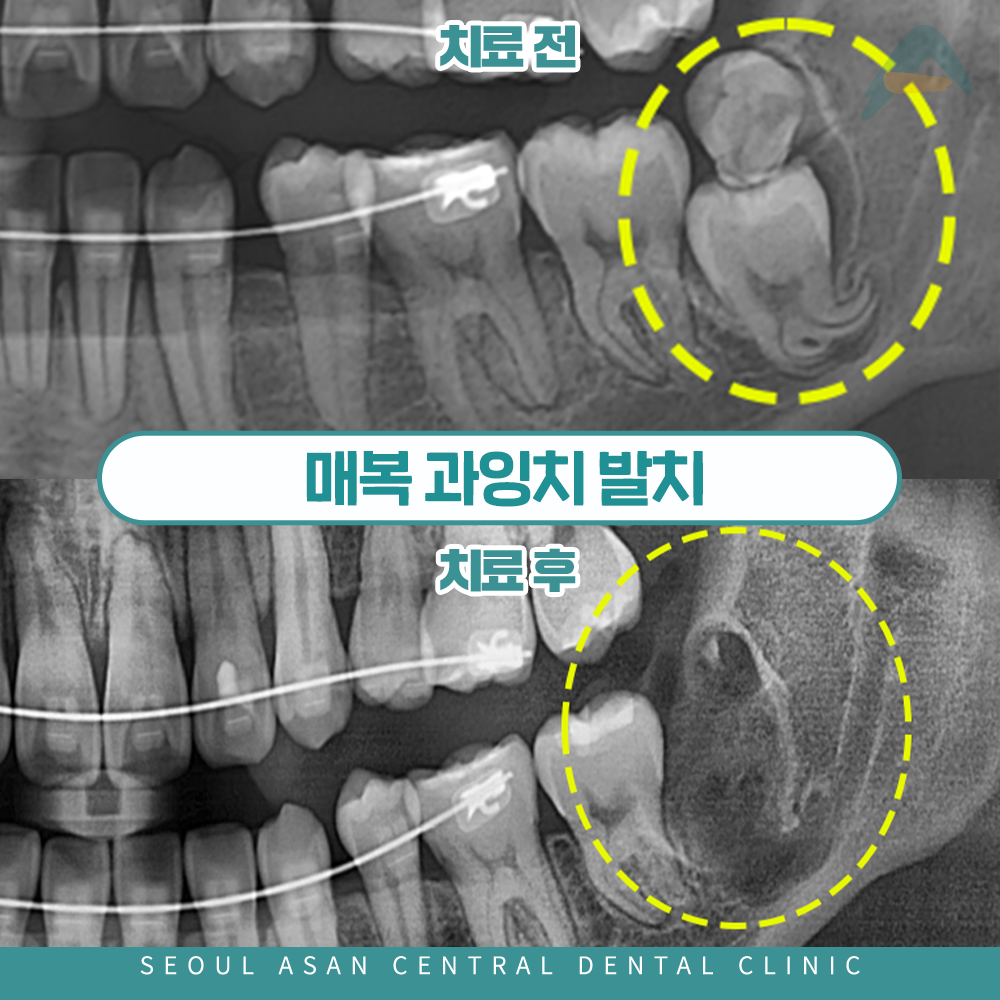

하악 좌측 부위에 매복된 사랑니와

과잉치가 인접 치아를 밀어내며

잇몸 염증과 반복적인 통증이 나타날 수 있는데요.

사랑니와 함께 매복된 과잉치가 동시에 존재하는 경우,

인접한 제2대구치(어금니)를 밀어내어

치열을 흐트러뜨리거나 잇몸 염증,

통증 등의 문제를 유발할 수 있습니다.

실제로 이러한 압력으로 인해

어금니가 손상되거나 저작하는 기능에까지

영향을 줄 수 있기 때문에,

상황에 따라 두 치아 모두

발치가 필요할 수 있습니다.